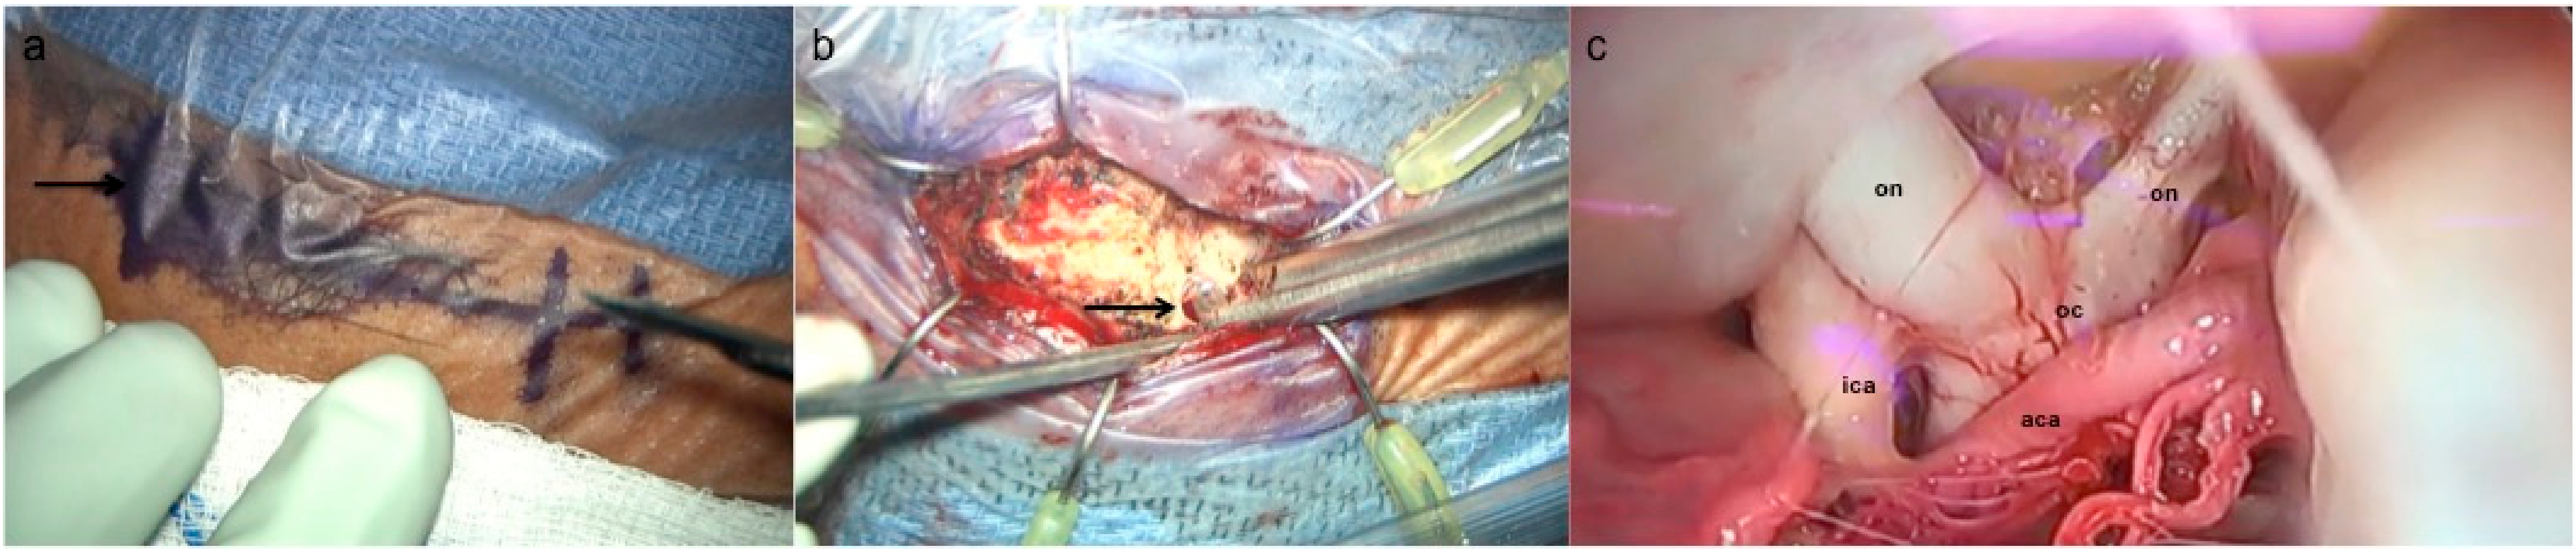

3.2. Supraorbital Craniotomy